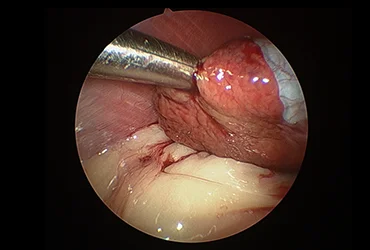

4. 간염 및 간경변증

간세포의 염증과 섬유화로 인한 간 기능 저하를 조기에 진단하고 관리합니다. 만성 간질환의 진행을 늦추고 합병증을 예방하기 위한 치료를 시행합니다.

(진단/협진 사례: 간염 환자의 복강경 생검, 간종양 환자의 경우 외과 협진을 통한 복강경 종양 제거 계획 수립)

치료 과정에서 외과와의 긴밀한 협력을 통해 담낭 절제, 종양 제거, 장관 이물 제거 등 필요한 수술적 처치를 원활하게 연계하며,